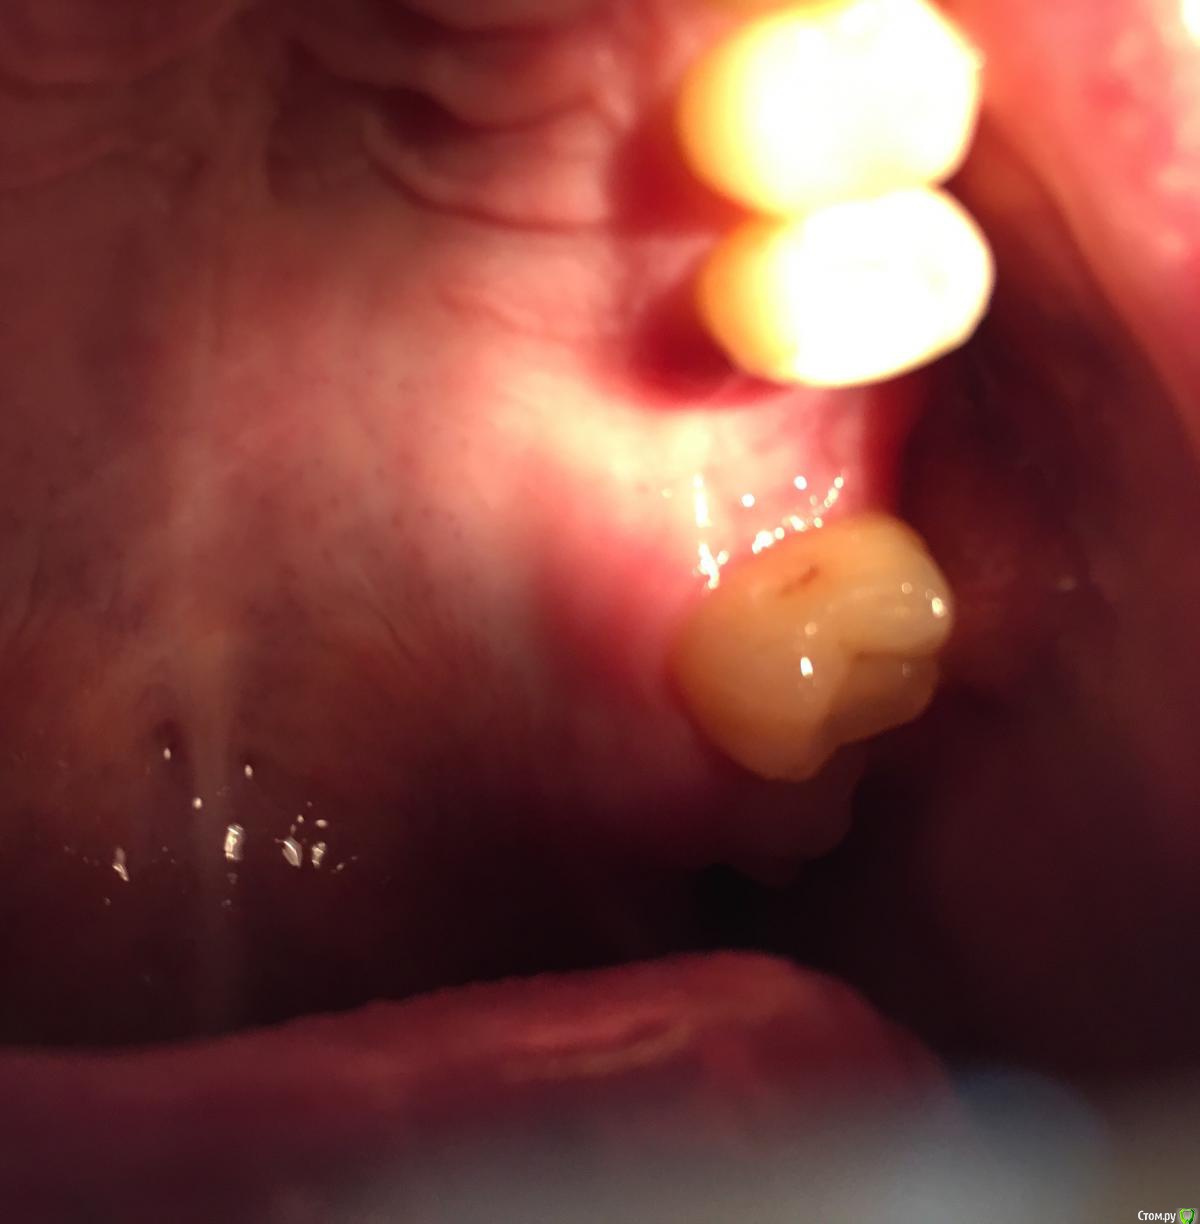

Bier Опубликовано 3 августа, 2018 Поделиться Опубликовано 3 августа, 2018 Точки болеть не могут, трогать их не нужно.Альвеолит может быть. Как лунка то выглядит? 1 Ссылка на комментарий

Павел10538 Опубликовано 3 августа, 2018 Автор Поделиться Опубликовано 3 августа, 2018 . Ссылка на комментарий

Павел10538 Опубликовано 3 августа, 2018 Автор Поделиться Опубликовано 3 августа, 2018 (изменено) Сфотографировал как получилось. Где то внутри какие-то жжения идут. Изменено 3 августа, 2018 пользователем Павел10538 Ссылка на комментарий

Bier Опубликовано 3 августа, 2018 Поделиться Опубликовано 3 августа, 2018 попробуйте небольшое зеркало найти и сфоткать отражение в нем. Вообще лунка вроде выглядит хорошо. 1 Ссылка на комментарий

Павел10538 Опубликовано 11 августа, 2018 Автор Поделиться Опубликовано 11 августа, 2018 (изменено) https://ru.files.fm/u/wt4uz2sdВот на КТ ссылку разместил. Пятерку пролечили, поставили пломбу. Врач когда на пятерку пломбу ставил сказал что экзостоз есть на десне бывшего шестого зуба. С внешней стороны. Языком чувствуется бугорок. Но он вроде снаружи, а боль внутри. В лунке. Изменено 11 августа, 2018 пользователем Павел10538 Ссылка на комментарий